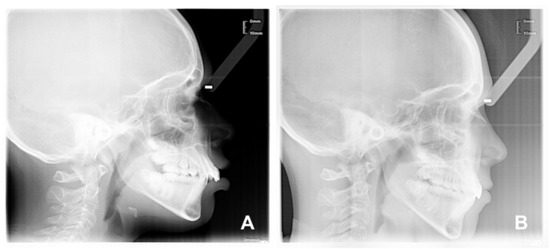

- Vertical skeletal outcomes: a significant increase in PFH/AFH (3.13, p = 0.0004), a reduction in Sna-Snp^Go-Gn (−2.51°, p = 0.0146) and S-N^Go-Gn (−2.87°, p = 0.0014);

- Sagittal skeletal outcomes: a significant mandibular advancement, SNB (2.17°, p = 0.0015) and a reduction in the ANB angle (−2.28°, p = 0.0001). On the contrary, no significant variation in the maxillary position, SNA, was noticed (−0.04°, p = 0.9484);

- Growth pattern outcomes: a significant reduction in the gonial angle, Ar-Go-Me (−3.13°, p = 0.0185), while there were no significant differences in the sellar (N-S-Ar −1.56°, p = 0.1141) and articular angles (S-Ar-Go 1.34°, p = 0.4442);

- Dental outcomes: an OVJ reduction (−2.64 mm p = 0.0002) without significant changes in the incisors inclination and position: Is^Ii (1.62 p = 0.4836); Is:NA (0.58 mm, p = 0.2822); and Ii:NB (0.92 mm, p = 0.0524);